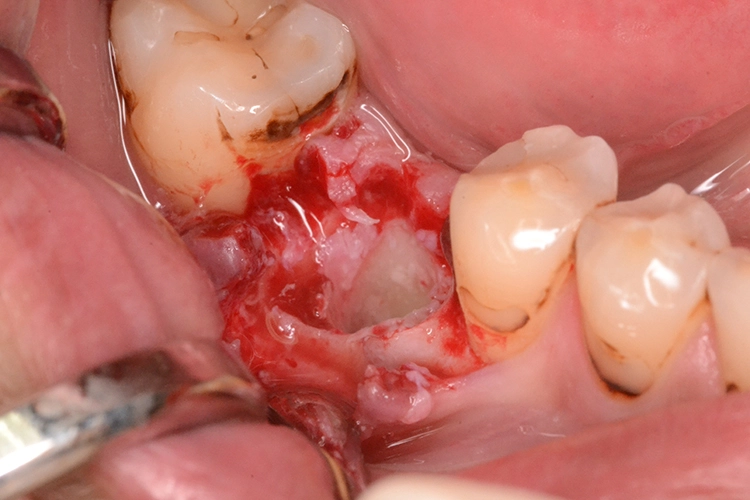

Im präoperativ angefertigten DVT (Abb. 3b und c) zeigte sich um die Wurzelspitze ein chronisches Entzündungsgeschehen, welches die vestibuläre Lamelle im apikalen Wurzelbereich des Zahnes 23 komplett aufgelöst hat. Da jedoch der Bereich direkt apikal von 23 nicht vom Geschehen betroffen war, fiel die Entscheidung zur Sofortimplantation auch, da der Patient blutverdünnende Medikamente einnehmen musste, welche durch Kombination von Extraktion und Implantation nur einmal abgesetzt werden mussten. In diesem Fall war aufgrund des Knochendefektes die Bildung eines Volllappens mit Entlastung unumgänglich.

Anschließend wurde der Knochendefekt mit kortikospongiösem Knochengranulat aufgefüllt und mit einer langsam resorbierenden Kollagenmembran versorgt (Abb. 3e und f). Das OP-Gebiet musste im Anschluss aufgrund der Augmentation vollständig gedeckt werden (Abb. 3g).